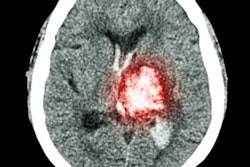

Brainomix said it has nearly doubled its overall team in the last six months, adding new software engineers, clinical specialists, and program managers to support expansion into new markets and new therapeutic indications such as lung fibrosis and cancer. Future appointments are also expected by the end of 2022.